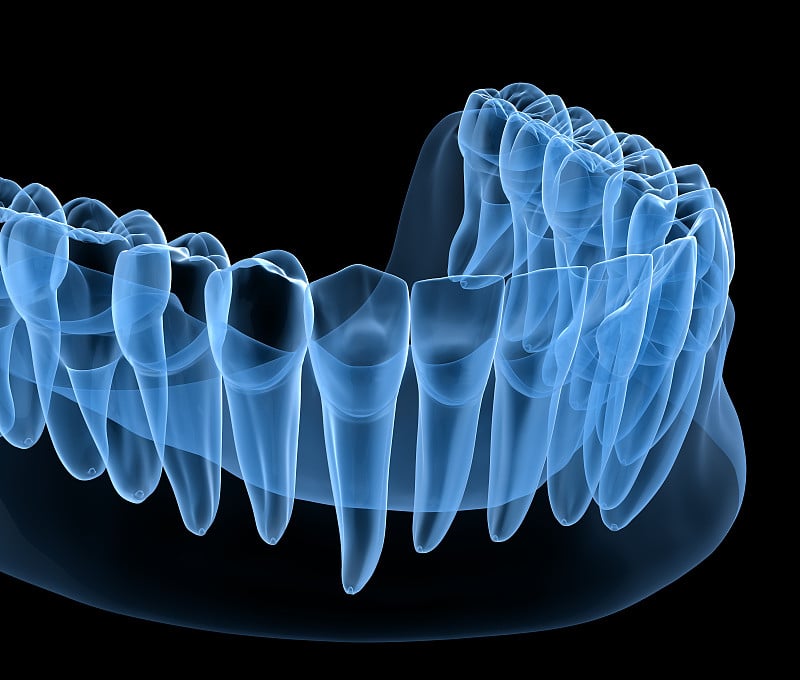

牙齿解剖详情

EPS